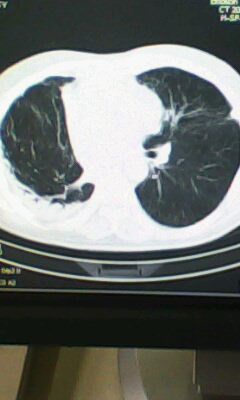

两肺感染性病变,右侧肺膨胀不全,左侧上叶结节影及左侧颈部淋巴结肿大建议复查。

右肺癌切除术后。

右肺炎症,左肺炎症。

右侧胸膜肥厚。

两肺感染性病变\\右侧胸膜增厚

术后改变,双肺内纤维索条影考虑与放疗有关。